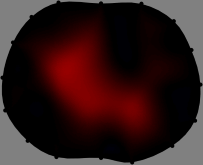

for [23]. This shows that the column vector is like an EEG (electroencephalography) data induced by dipole sources with directions at locations . Given that two dipole sources at distant locations produce mutually independent data, the correlation between and decreases with the distance between and . Fig. 2 shows a few images of the correlation as a function of for four different positions . The correlation decreases rapidly as the distance increases. In the green regions where the correlation is almost zero, is nearly orthogonal to .

Fig. 2 shows that if and are far from each other, the corresponding columns of the sensitivity matrix are nearly orthogonal. This somewhat orthogonal structure of the sensitivity matrix motivates an algebraic formula that directly computes the local ensemble average of conductivity changes at each point using the inner product between changes in the data and a scaled sensitivity vector at that point: